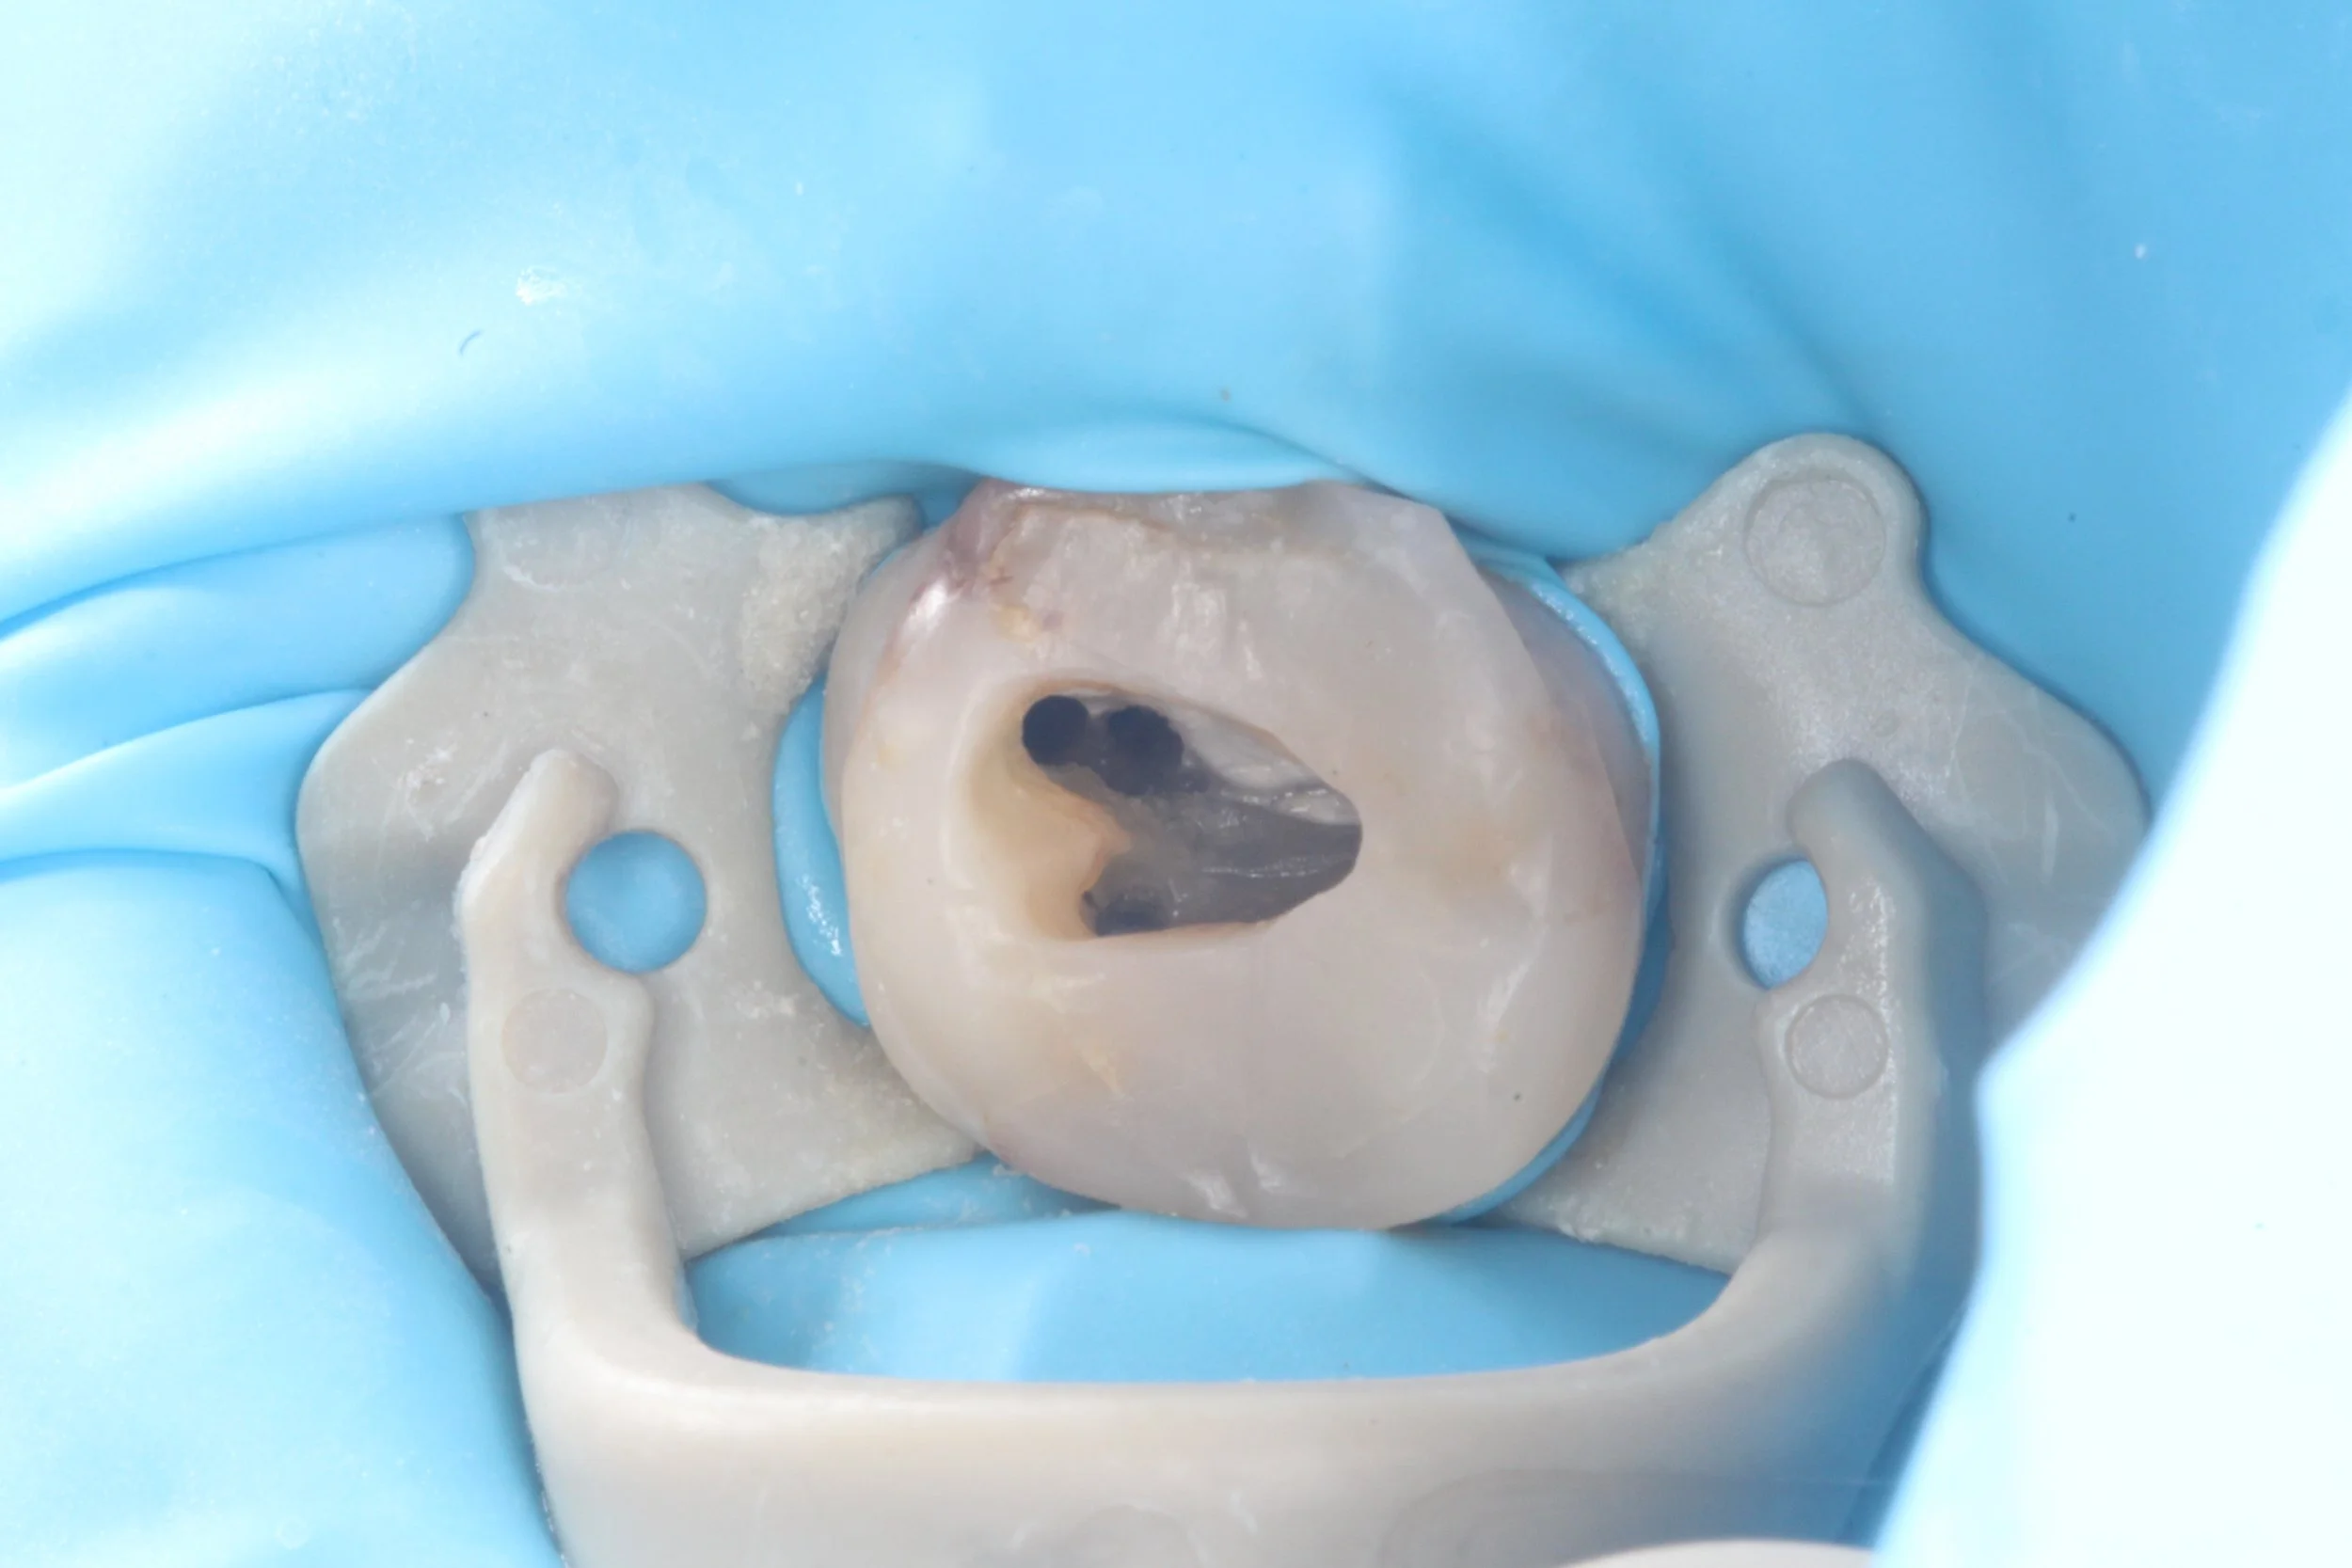

Access cavity in upper second molar. Extremely aberrant position of MB2 orifice, positioned closer to P orifice than MB1 orifice.

Access cavity in upper first molar LHS. Initially only a singular MB orifice could be found along the floor of the pulp chamber. This single orifice split into two separate MB1 and MB2 canals, about 2mm apical to the pulp chamber floor.